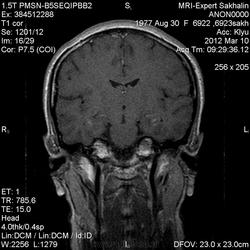

Провели дополнительное контрастирование:

С лимфомой верифицированной не встречался, картина не противоречит паранеопластическому или герпетическому энцефалиту. Склероз гиппокампов: нет уменьшения их размеров, зоны изменений сигналов гиппокампами не ограничиваются, есть кроме височных долей и в ножках мозга, опять же накопление контраста.

Думаю, что следует дифференцировать между энцефалитом и опухолевым процессом. В общем я не оригинален, соглашусь с уже высказанными мнениями. Впрочем первый как то не сильно укладывается по клинике, а для второго мультифокальность как то не сильно "катит". МР-динамика, пункция, что еще можно порекомендовать...

Еще гайморит тут правосторонний, может это несколько качнет весы в сторону воспалительного процесса?

Для И.Бондаренко - вы все правильно указали - гипер- в Т2W, а также гипо- в Т1W, + очаги накопления контраста

Есть и давно подтвержденное понятие паранеопластический лимбический энцефалит - как вариант примерно так и будет выглядеть.

(не хватает данных DWI и желательно при таких делать fatsat добавлять при контрасте как то лучше накопление по оболочкам видно, также не помешало бы и Т1mgt ну или двойную/тройную дозу контраста)

В данном случае больше данных за воспалительный энцефалит - есть синусит (не нравиться гиперинтенсивное включение парацентрально в пазухе -грибок????) .

С учетом накопления контраста да и по локализации однозначно не опухоль, не инсульт, не травма. Из классики да действительно герпес любит виски, также и иные вирусные могут быть (этиологию иной раз не угадаешь - бессмыслено), может быть и тбс. но сос четов не сбрасывал бы паранеопластический - тем более женщина да и контраст накопила как бы не молочка?? Ну и совсем чтоб запутать нет ли В20? только на внешний вид и на мужа не надо ориентироваться - у нас и у врачей и у студентов мед вузов бывает - пройденный этап(((

Была у нас пациентка (картинки предоставить не могу , так как поезд ушел) , картина была один в один , только в меньшей степени выраженности. Тоже возникло после перенесенной ОРВИ, после лечения приходила на контроль - мр- сигнал вернулся к норме. Так что согласна с энцефалитом. При паранеопластическом процессе все же более четкие границы , я так думаю. и распостраненность несколько другая..